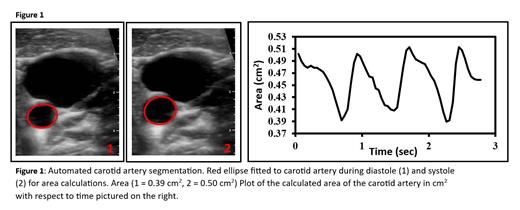

All participants had their vitals taken and their right common carotid artery imaged in supine position following at least 10 minutes rest. Imaging was performed by an experienced imaging professional (AB, 10 years experience) using a Butterfly IQ + ultrasound probe (Burlington, MA) and an Apple smartphone (Cupertino, CA) in the B-mode vascular setting. Three to ten second recordings of the carotid artery were recorded at a rate of approximately 20 frames per second. In house MATLAB scripts were developed for semiautomated cross sectional area segmentation across the cardiac cycle to calculate vessel lumen area (Figure 1). Strain was calculated using the ratio of change in systolic and diastolic area over diastolic area, and distensibility (1/stiffness) was calculated as strain/ln[SBP/DBP] (Godia, 2007). Univariate and stepwise multiple analysis was performed to determine the correlates of arterial distensibility.